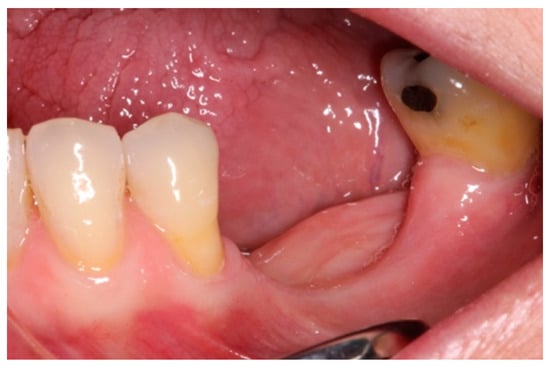

- On the day of surgery, the titanium mesh and the microscrews were removed (Figure 9). When the mesh was removed, a soft consistency was observed in the most coronally newly formed bone and it was decided to postpone the placement of the implants and allow it to ossify for another month and a half. A panoramic radiograph was taken after surgery (Figure 10).